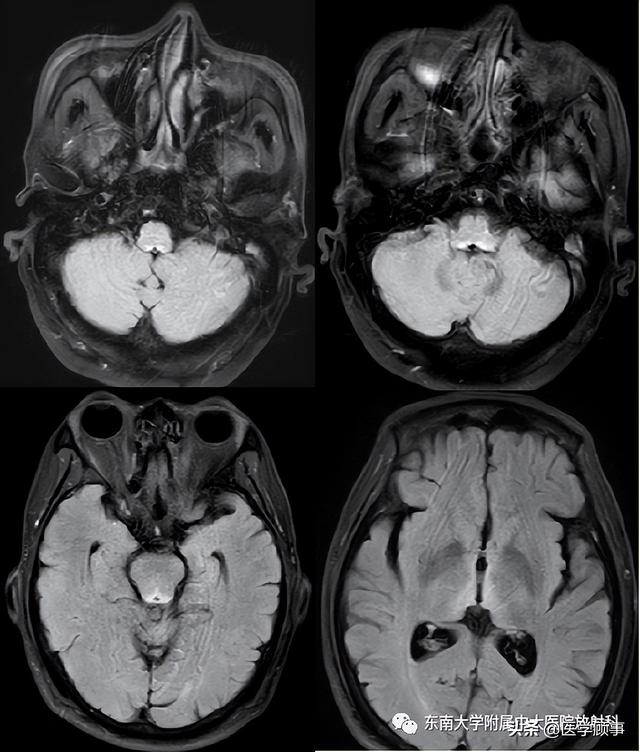

神经影像:韦尼克脑病在 swi 上的特征表现

wernicke脑病mri表现

wernicke脑病的影像特点